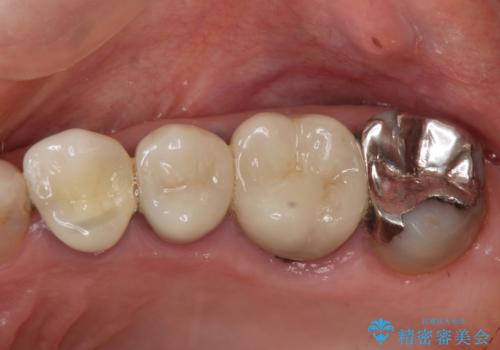

銀歯や古くなったクラウンをやりかえたい

- 違和感や疼きのある左側小臼歯に加え全体的にクラウンや詰め物のやりかえを希望され来院されました。

X線写真検査ではわからない虫歯も外してみると再発していることがあります。虫歯を丁寧に取り除き、再発を防ぐべく精密なクラウンの作製を行うことが長期的な予後につながります。